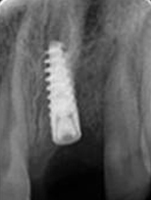

X-ray of Implant

Placement of Bone Grafting

X-ray of Implant + Abutment

X-ray of Implant +

Abutment+ Prosthesis